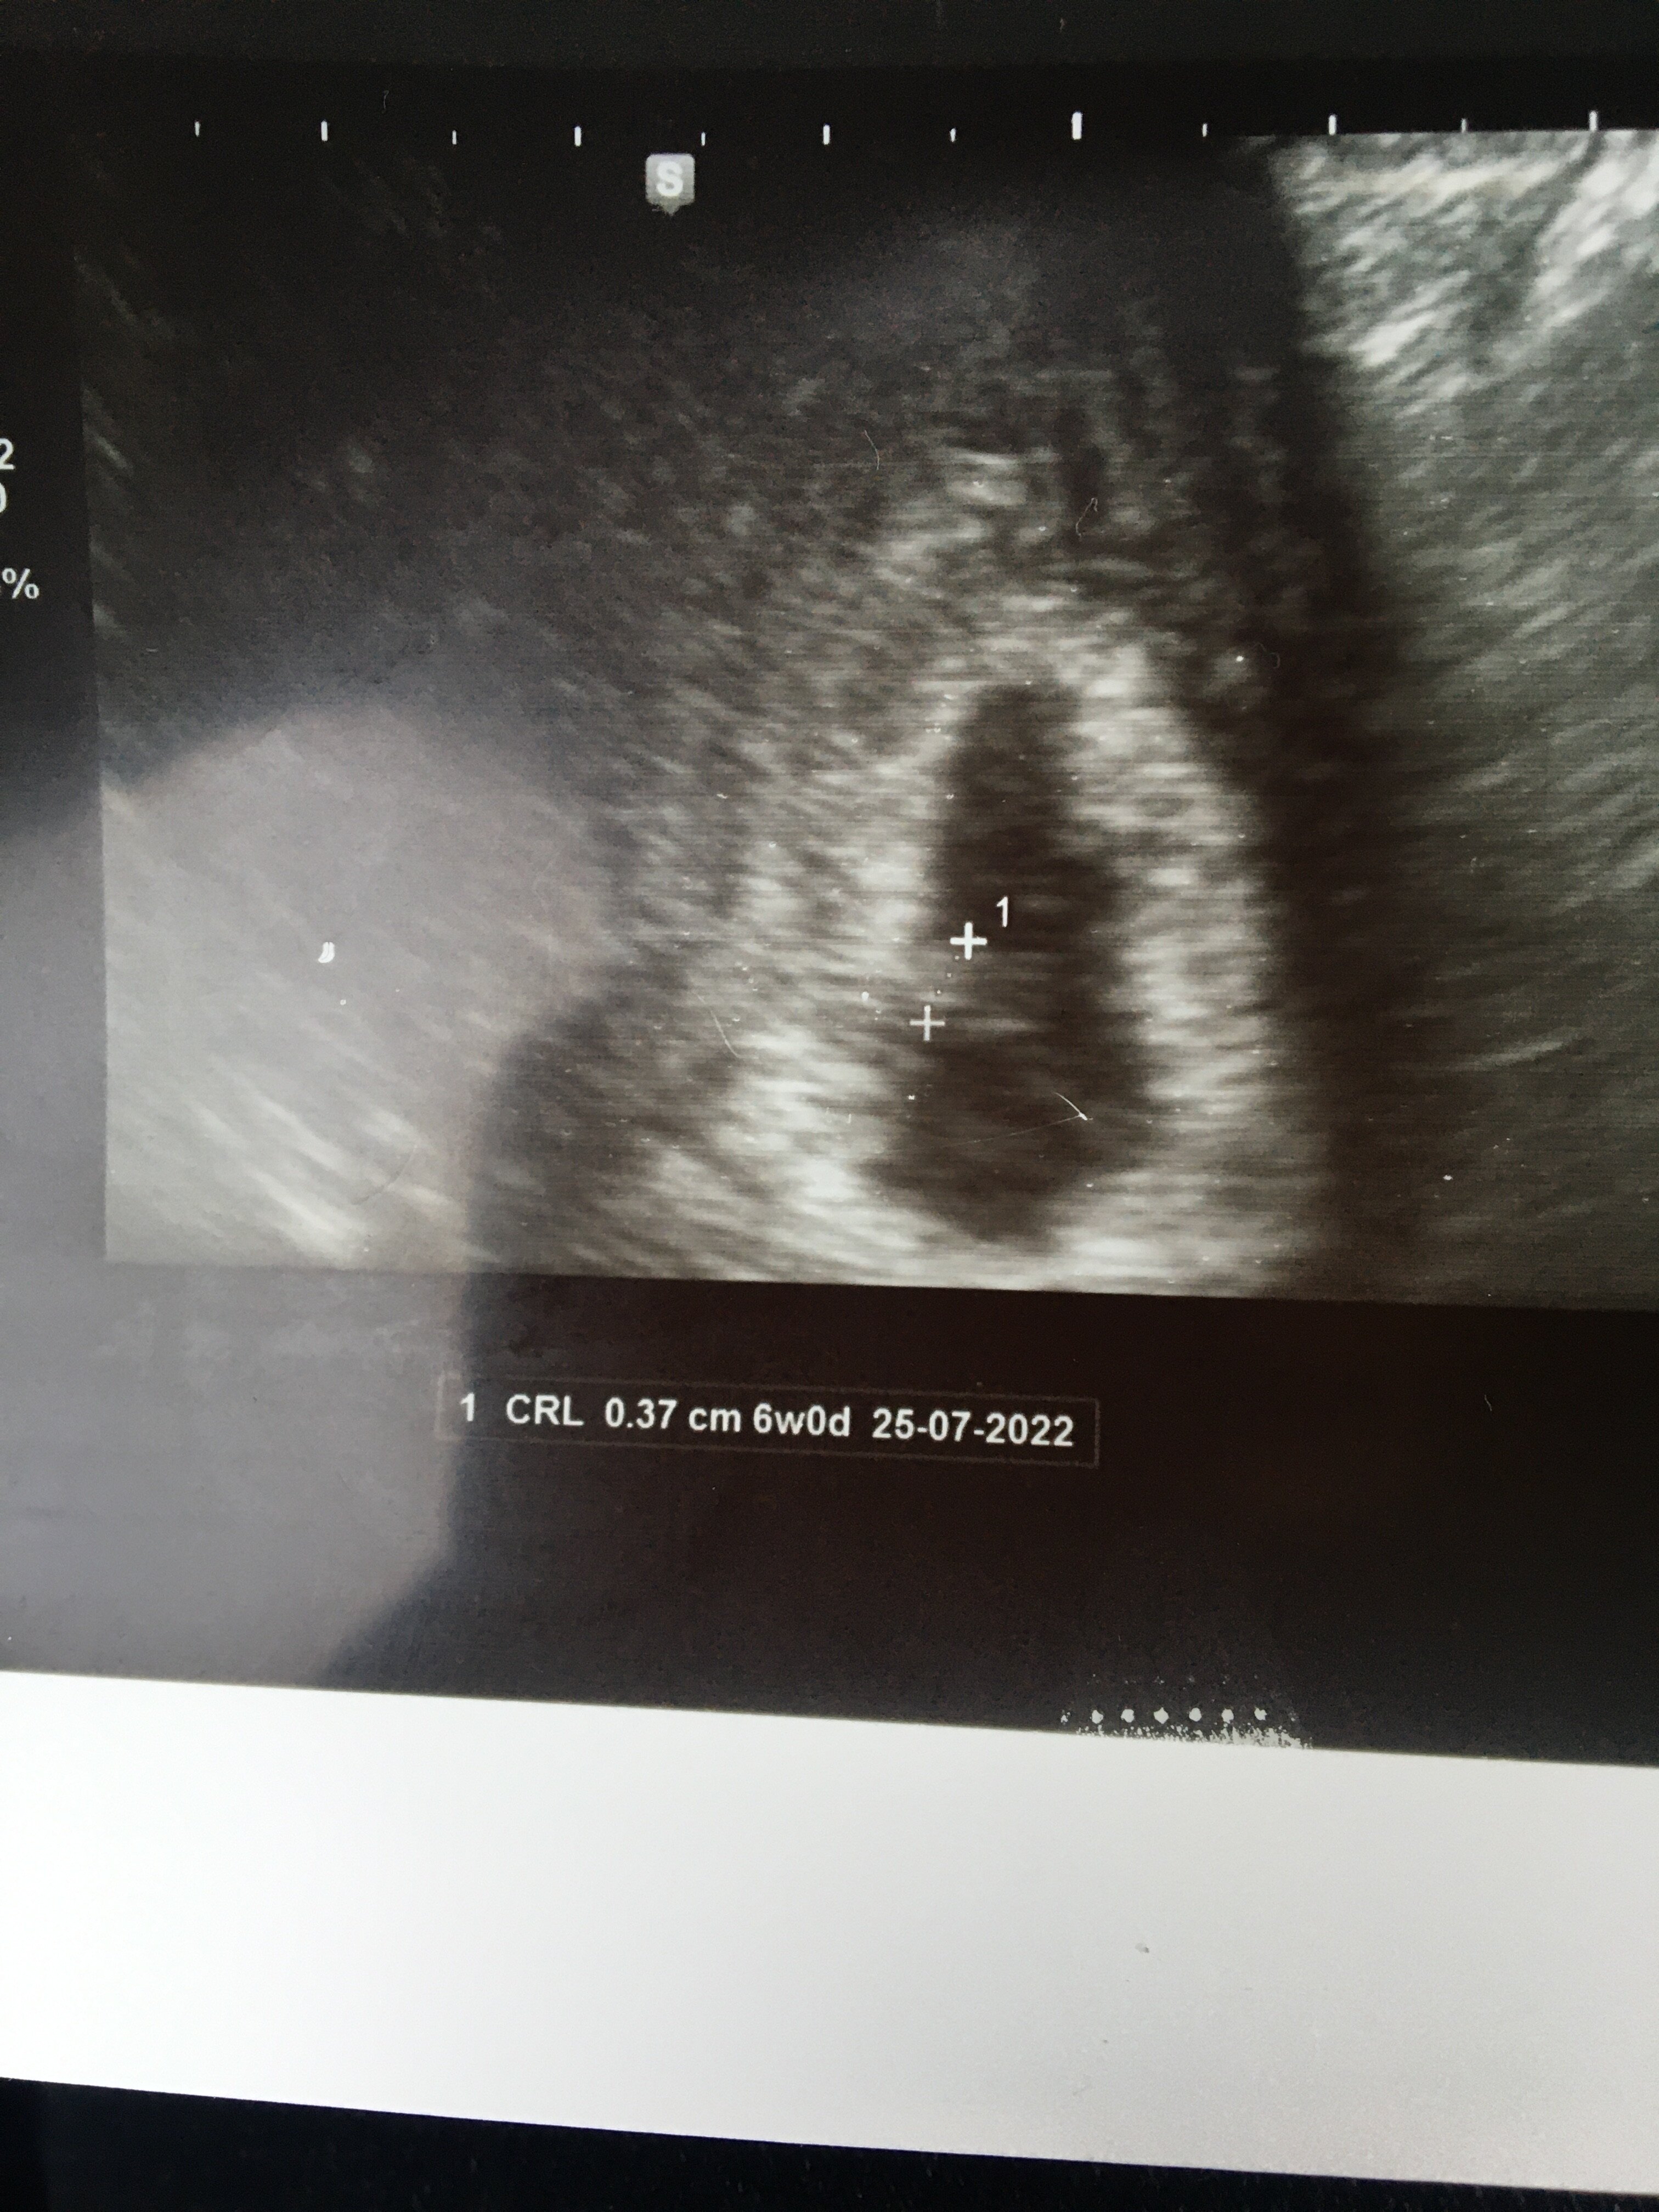

Ja już tez po wizycie, mój lekarz ma słaby sprzęt, mało widać. Według usg 6tc, zarodek widać o serduszku nic nie mówił ale mówił ze wszystko dobrze. Ze względu na wcześniejsze poronienie mam włączony acard 150 i clexane 0,4 do Ok 13 tygodnia. Następna wizyta 16.12 ale jak mu powiedziałam ze do tego czasu zejdę na zawał to stwierdził ze mam zadzwonić o wcześniejsza wizytę jak bardzo bede się stresować 😂

Uff Ja po wizycie troszkę była obsuwa i weszłam po 10 i dopiero do domu zladowalam bo jeszcze zakupy itp. A na 14 do pracy lecę 😁 ale do żeczy po wizycie wszystko w jak najlepszym porządku 🥰🥰🥰🥰 mały człowiek ma 2cm 😁😁😁😁😁i mamy dziś 8tydziien według @ i pomiarów z usg